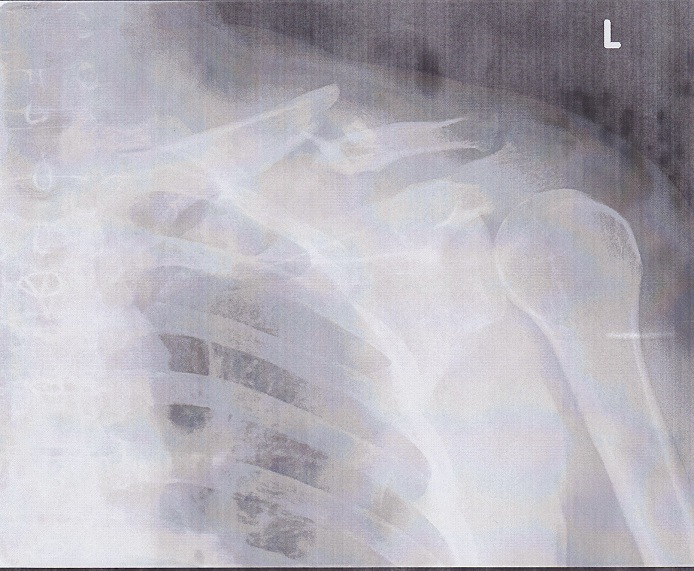

手術前

レントゲン写真の白黒コピーなので、かなりわかりずらいが。

ほぼ真ん中で分断されて、さらに小さい骨片が2つ上を向いている。

胸に近い方の骨は本来あるべき角度ではなく上方を向いている。

肩側の骨の角度は正常らしい。肩の腱で固定されてるからか???

胸元から鎖骨を指先で伝うと、明らかに本来骨のある場所でないところに骨があり、

それが途中で途絶えているのがわかる。

開放骨折の一歩手前なのかなぁ・・・